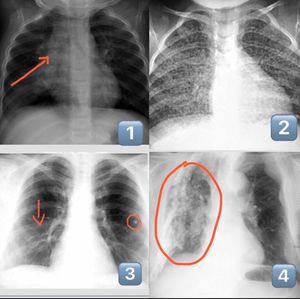

This weeks topic I'm presenting is Tuberculosis. Above you can see four possible radiological findings in pulmonary Tuberculosis (TB). 1. Lymphadenopathy due to primary TB 2. Miliary TB may be observed in primary and Post-primary TB 3. Ghon focus (calcification) as outcome of primary TB 4. Huge cavitations and calcifications as outcome of post-primary TB Tuberculosis is still a disease not only developing countries are fighting. Some European countries have difficulties treating tuberculosis because of highly resistant forms. Tuberculosis is caused by Mycobacterium tuberculosis spreading through air via droplets. Active and latent TB is differentiated as only active TB is contagious. Especially immune suppressed patients (HIV/AIDS, iv drug users/ alcoholics, certain cancers) are prone to develop tuberculosis. Intense exposure to micro organism may infect healthy as well. Healthcare workers in permanent contact with infected people are at high risk of developing this condition. Symptoms include coughing up blood, chest pain, chills, night sweats. As tuberculosis might affect other organs blood in urine or back pain can also be experienced. TB can be diagnosed by a tuberculin quick-test or more recently Gamma interferon Test, x-ray of lungs and for definitive diagnosis culture of Mycobacterium tuberculosis. Clinically we differentiate between Primary and Post-primary TB which will be discussed later this week.